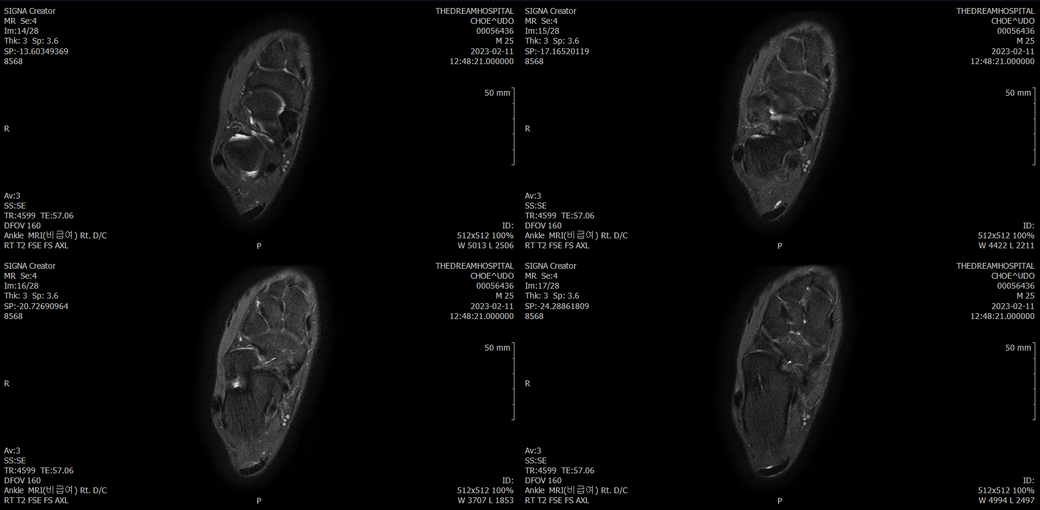

오른발목 mri 전체사진입니다. 제가 병원을 갈수없는상황인지라.... 봐주시면 감사하겠습니다.

엑스레이에서는 문제가 없다고 하여 오른발목 mri촬영했습니다.

• 1번 째 사진

• 2번 째 사진

• 3번 째 사진

• 4번 째 사진